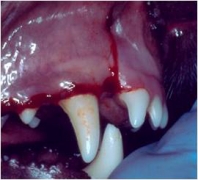

Otro problema muy común en perros es la presencia de fístulas oronasales. La fístula oronasal es una comunicación patológica de la cavidad oral con la cavidad nasal. Regularmente el paciente muestra una rinorrea unilateral que puede ser serosa, mucosa o sanguinolenta. Clínicamente se observa una pequeña abertura en la cavidad oral de la cual puede salir una secreción serosa, mucosa o sanguinolenta. La cavidad puede estar llena de pelo y detritus aunque algunas veces es poca su contaminación. La abertura es la punta de un iceberg, ya que la lesión ósea es regularmente mucho mayor. Se tiene la creencia de que puede cerrarse quirúrgicamente manejando solo los tejidos blandos pero eso es imposible. Se requiere un tratamiento quirúrgico de manejo combinado de tejidos duros y blandos para poder cerrar la fístula. Las fístulas oronasales pueden invadir el globo ocular, el seno maxilar y la cara, por lo que es muy importante realizar un diagnóstico temprano y la rápida resolución quirúrgica del defecto. El manejo de tejidos requiere realizar la extirpación total del tejido patológico de la cavidad nasal y de otras estructuras invadidas. Se requiere además de la ostectomía del tejido involucrado con una osteoplastia en donde los bordes del defecto óseo deben quedar sin ángulos cortantes y bien limados. Regularmente se requiere realizar colgajos de avance o de la forma mejor adaptable dependiendo del defecto. Otro problema poco común de origen congénito es la presencia de paladar hendido el cual puede ser ligero hasta muy severo. Estos casos regularmente se manejan como si fueran fístulas oronasales pero hay que tener cuidado con la elección en la decisión de preservar la vida de un espécimen en estas condiciones porque son pacientitos que nunca van a tener un desarrollo adecuado excepto de que el defecto sea lo suficientemente pequeño para cerrarlo en una sola intención.

Haz CLICK sobre la imagen para ver descripción.Cierre de fístula Oronasal

Fístula Oronasal en un caniche